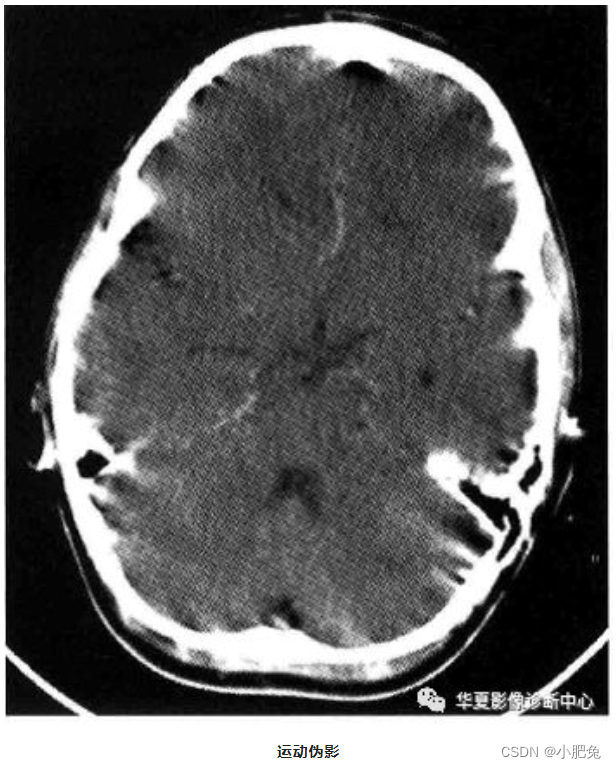

一、患者运动伪影

与患者有关的伪影有随意的和非随意的,随意的运动有扫描时呼吸和吞咽运动, 不随意的有心跳 、 肠蠕动等, 它们在图像中的表现均是条状伪影。 其产生的原因是由于运动部分的边缘体素衰减不一致 , 使即像重建无法处理而产生。

运动伪影往往可设法避免, 对千呼吸和吞咽运动 , 可在检查前根据CT机的呼吸指令训练患者屏气, 告知患者尽量不做吞咽动作 , 并伸舌、 轻咬住舌尖, 不但可抑制吞咽动作, 还可避免舌根后坠, 影响会厌蹊的观察; 其次在一些运动器官的检查中, 尽可能采用缩短扫描时间, 缩短扫描时间是减少运动伪影最有效的方法 ; 第三可利用CT机上的一些运动伪影抑制软件进行处理, 可有效减少运动伪影。